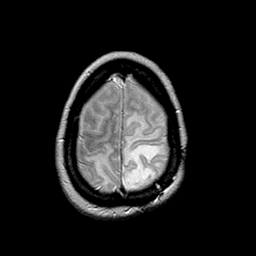

MR Study #2 -- Slice #44